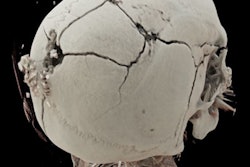

As for CT, its speed, subtle grayscale, and ability to depict 3D relationships are enormous advantages. Skeletal trauma, for example, can be depicted in ways that conventional autopsy can't replicate.

A close look at the 3D reconstructions can often separate a mortal wound from nonfatal trauma that only looks deadly, which makes the modality indispensable in forensic examinations, Volk said.

![]() |

| A traffic accident victim suffered from multiple fractures and died from a broken neck vertebra (below). Images courtesy of Dr. Anders Persson and Patric Ljung. |